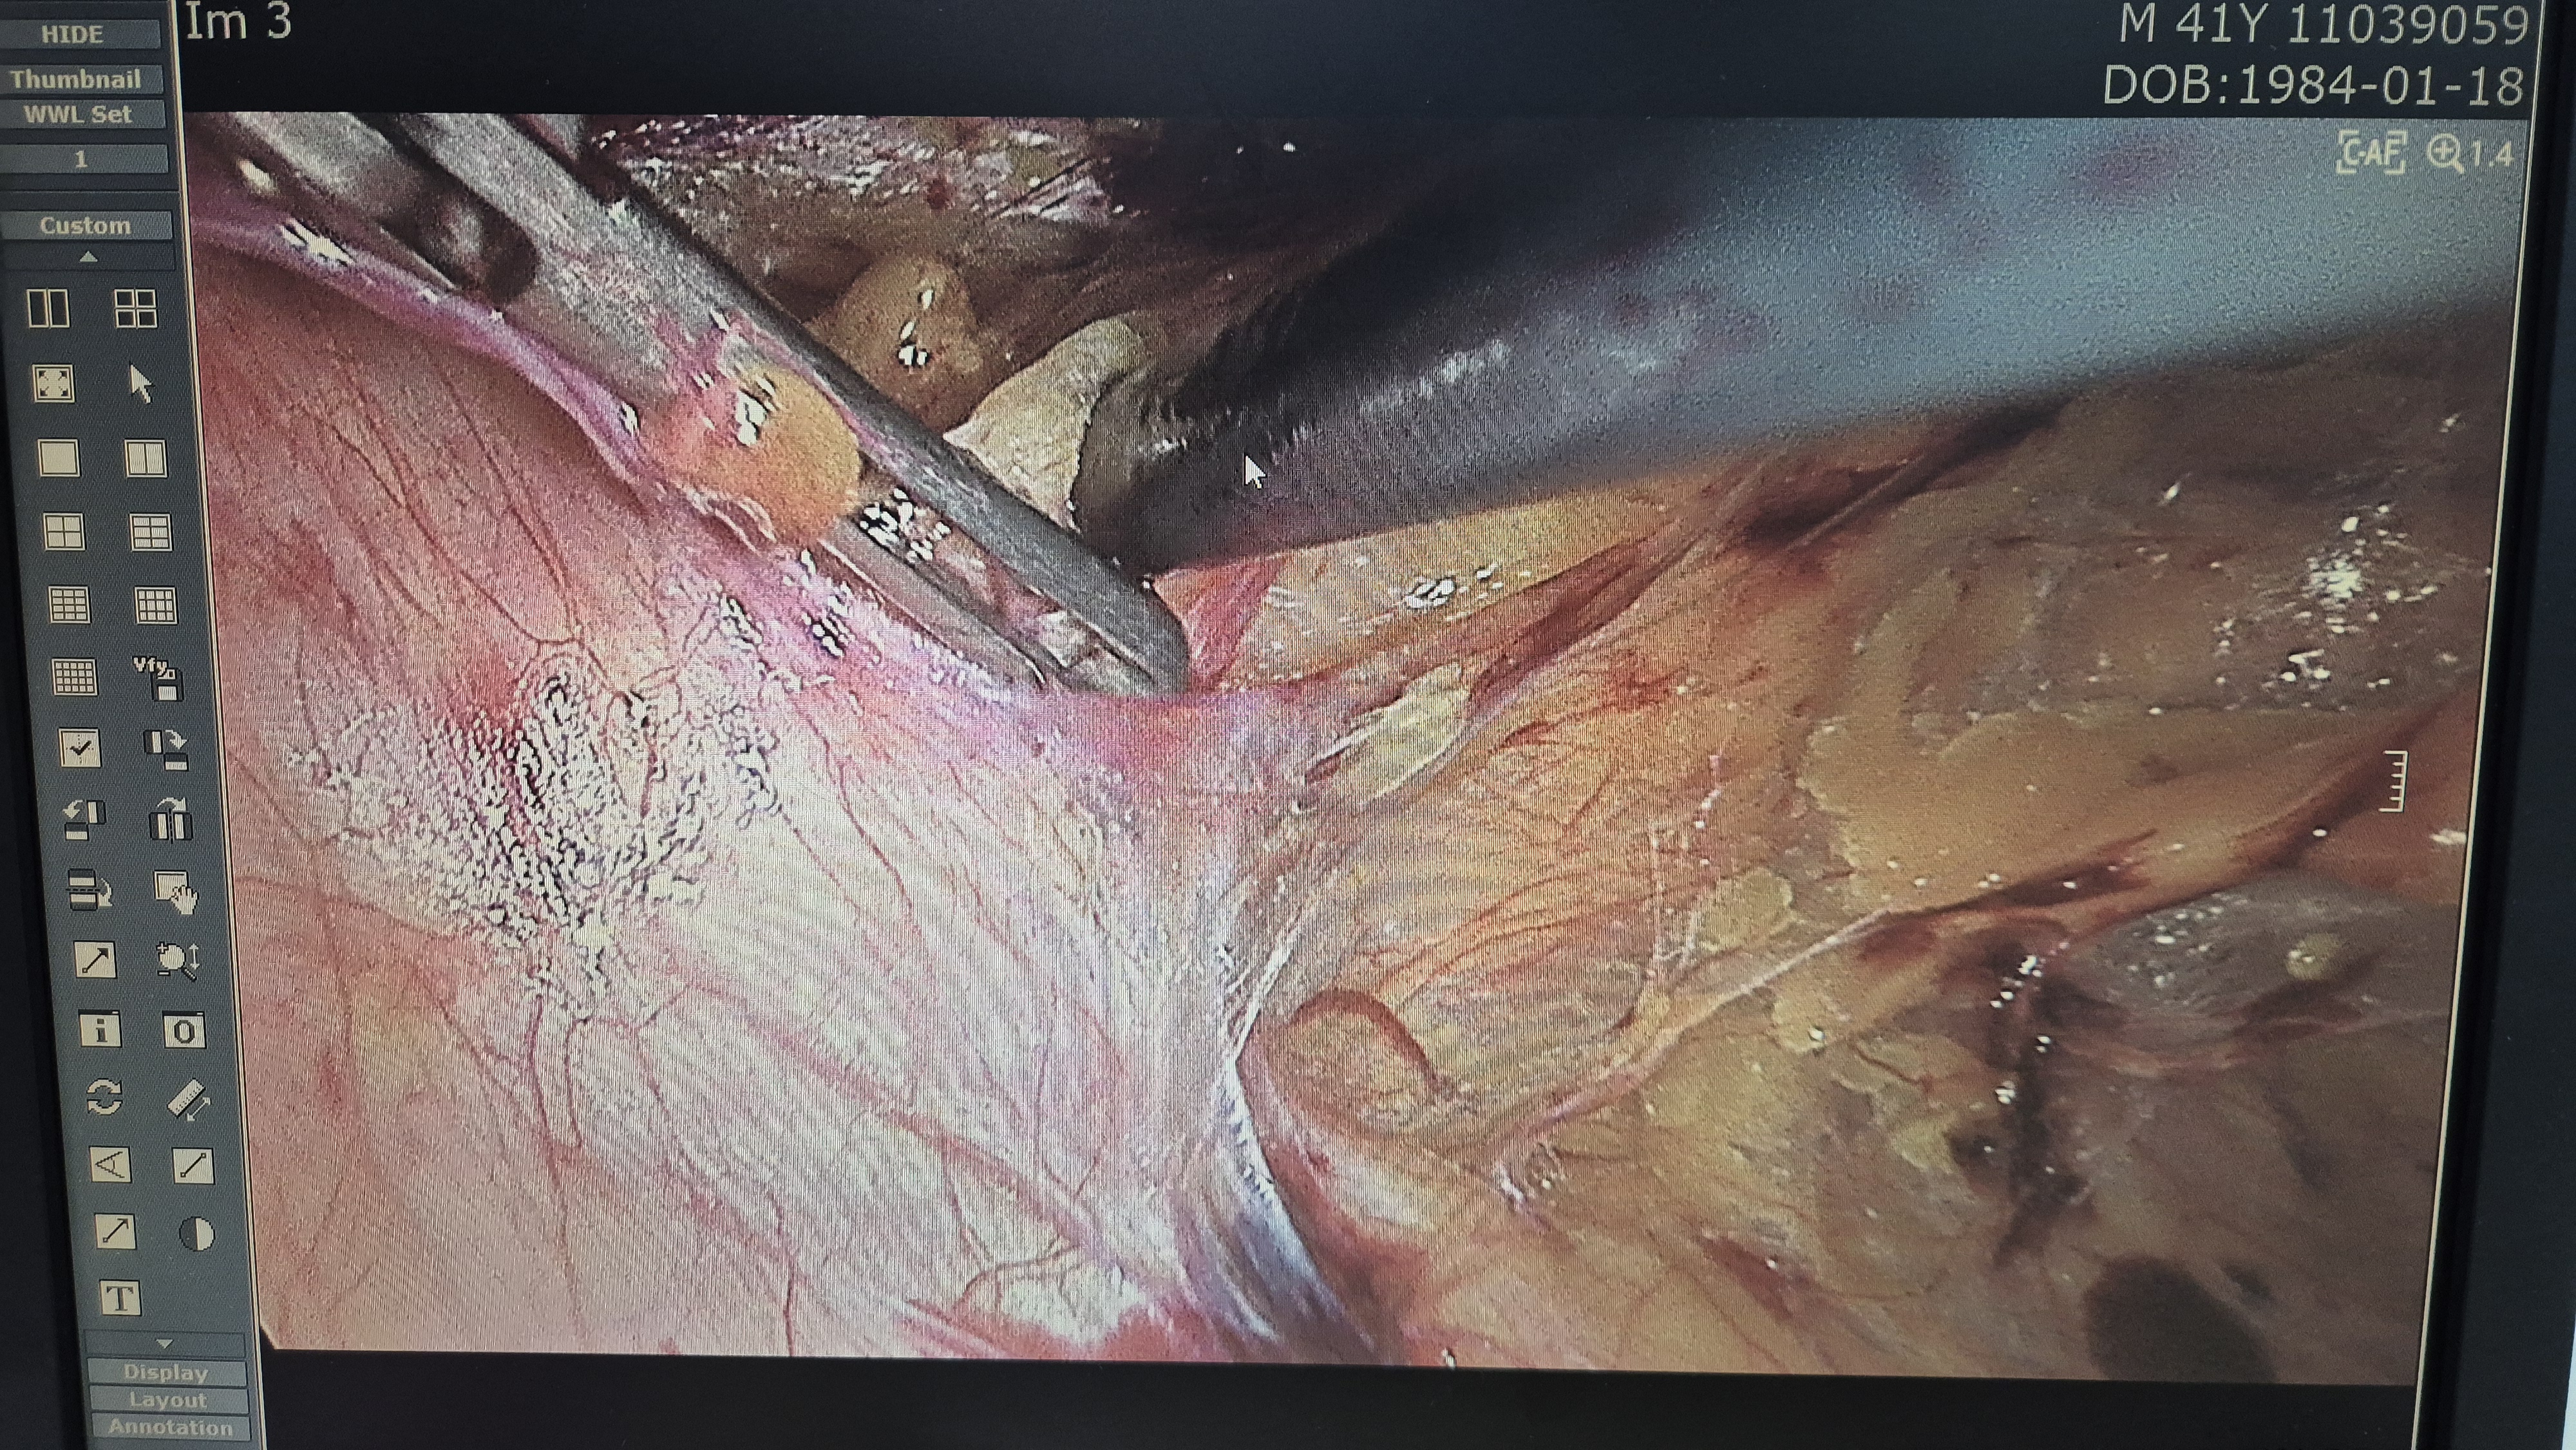

방금 복강경 탈장교정술을 시행했습니다.

탈장 확인후.

박리.

메쉬로 고정.

수술은 15분 걸렸습니다.